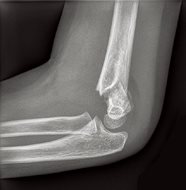

She was tearful, and used her right hand to hold her left elbow at a 45-degree angle for comfort and support. There was no tenderness over her left shoulder or wrist, and no abrasions or lacerations elsewhere on her body. Plain film radiographs of her left elbow were ordered (Fig. 1, a & b).

2. Acute, mildly displaced Type III supracondylar fracture with dorsal angulation of the distal humerus and associated joint effusion. (See below for further discussion of fracture types.)

These fractures are classified according to the Gartland classification system: type I, type II, and type III. In the simplest terms, type I is non-displaced, type II is displaced with an intact posterior periosteum and cortical continuity, and type III is displaced with disrupted anterior and posterior periosteum and lack of cortical continuity.2 This fracture is a type III because the AP projection shows lateral displacement. This could only occur if both the anterior and posterior cortices are broken.

Fig. 1a: Lateral view of left elbow.

Fig. 1b: AP view of elbow.